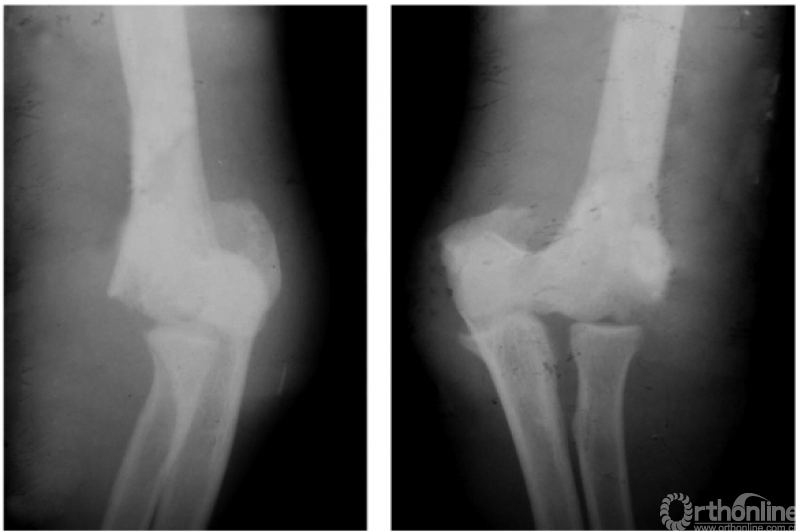

二、陈旧性肱骨髁上骨折

例1:陈旧性伸展型肱骨髁上骨折,致肘内翻畸形及前倾角消失(图7)。

图7